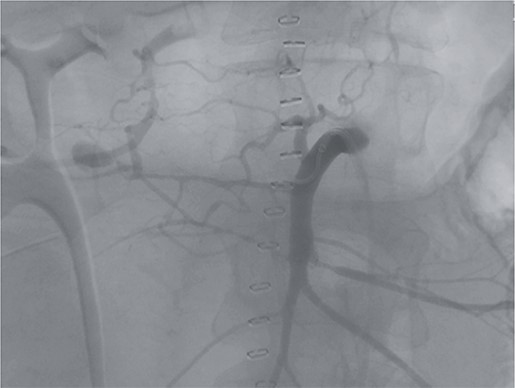

However, on the 16th day following the initial surgery, there was another active bleeding from the pancreaticoduodenal artery, distal to the previously placed coil. This bleeding was also managed interventionally (Figs 4 and 5).

Angiography showing another aneurysm with active bleeding, proximally to the previously coiled site.